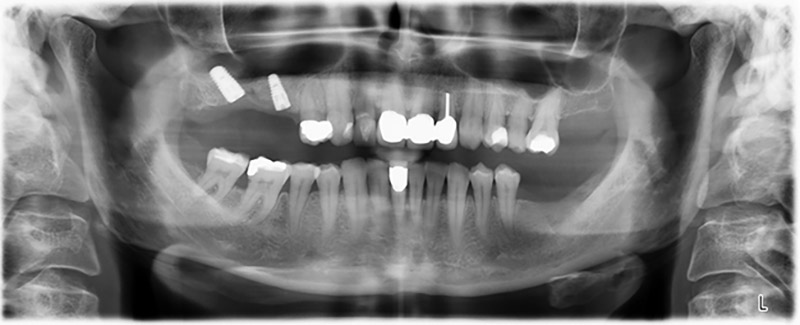

The 59-year-old patient presented with an advanced case of periodontitis, describing an unpleasant feeling and poor taste from the first quadrant in a distal direction. The clinical examination revealed generally enlarged periodontal pockets and very advanced bone atrophy in regions 16 and 14. The radiology confirmed the findings (Fig. 1). Teeth 16 and 14 could not be retained.

About six months after teeth 16 and 14 were extracted, a digital volume tomography (DVT, Planmeca) examination was performed for planning and risk minimization purposes. It clearly showed that the bone had not regenerated to the desired volume (Fig. 2 to 7).